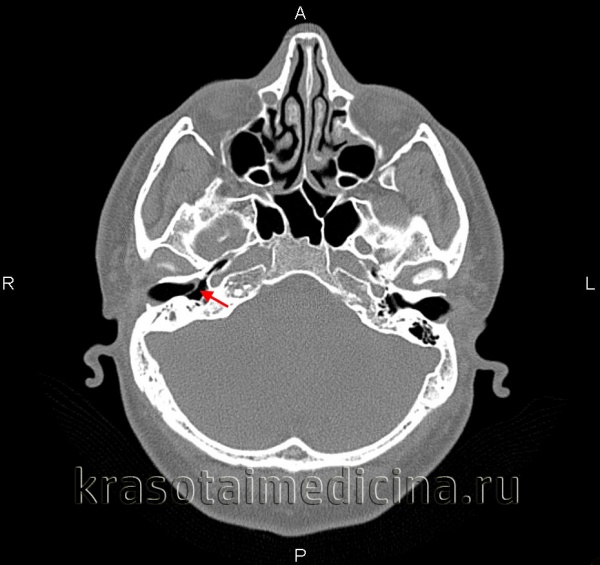

Происходящие при отосклерозе изменения костной ткани капсулы лабиринта иногда определяются по результатам прицельной рентгенографии черепа. Однако более информативным исследованием является КТ черепа, позволяющая визуализировать очаги отосклероза.

КТ височных костей. С обеих сторон диффузное снижение пневматизации ячеек сосцевидного отростка и пирамиды височной кости за счет отосклероза